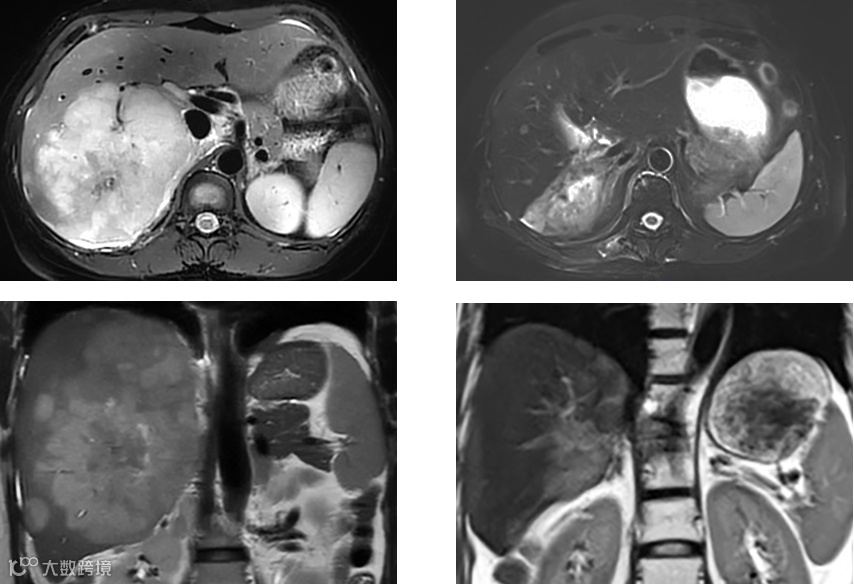

治疗前(左)、治疗后(右)